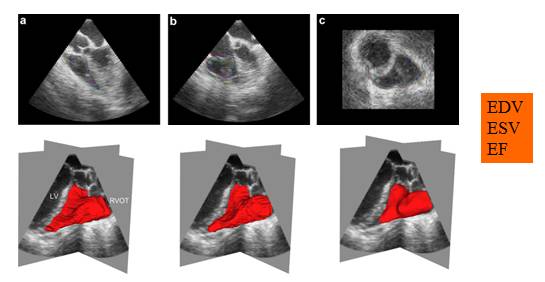

三维容积测定

四维右室功能法